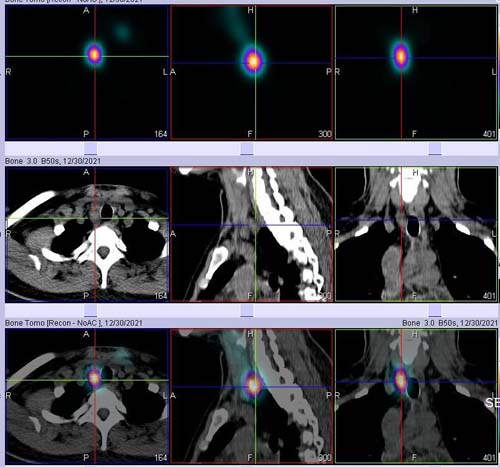

一名青年女性甲状腺乳头状癌术后,停优甲乐前查抑制性甲状腺球蛋白175.60 ng/ml。停优甲乐入院后查刺激性甲状腺球蛋白>500.00ng/ml。给予碘-131清甲兼顾清灶。碘扫描提示残甲、颈部及上纵膈多发淋巴结转移。出院1月后复查示抑制性甲状腺球蛋白降至5.30 ng/ml。

西门子SPECT/CT